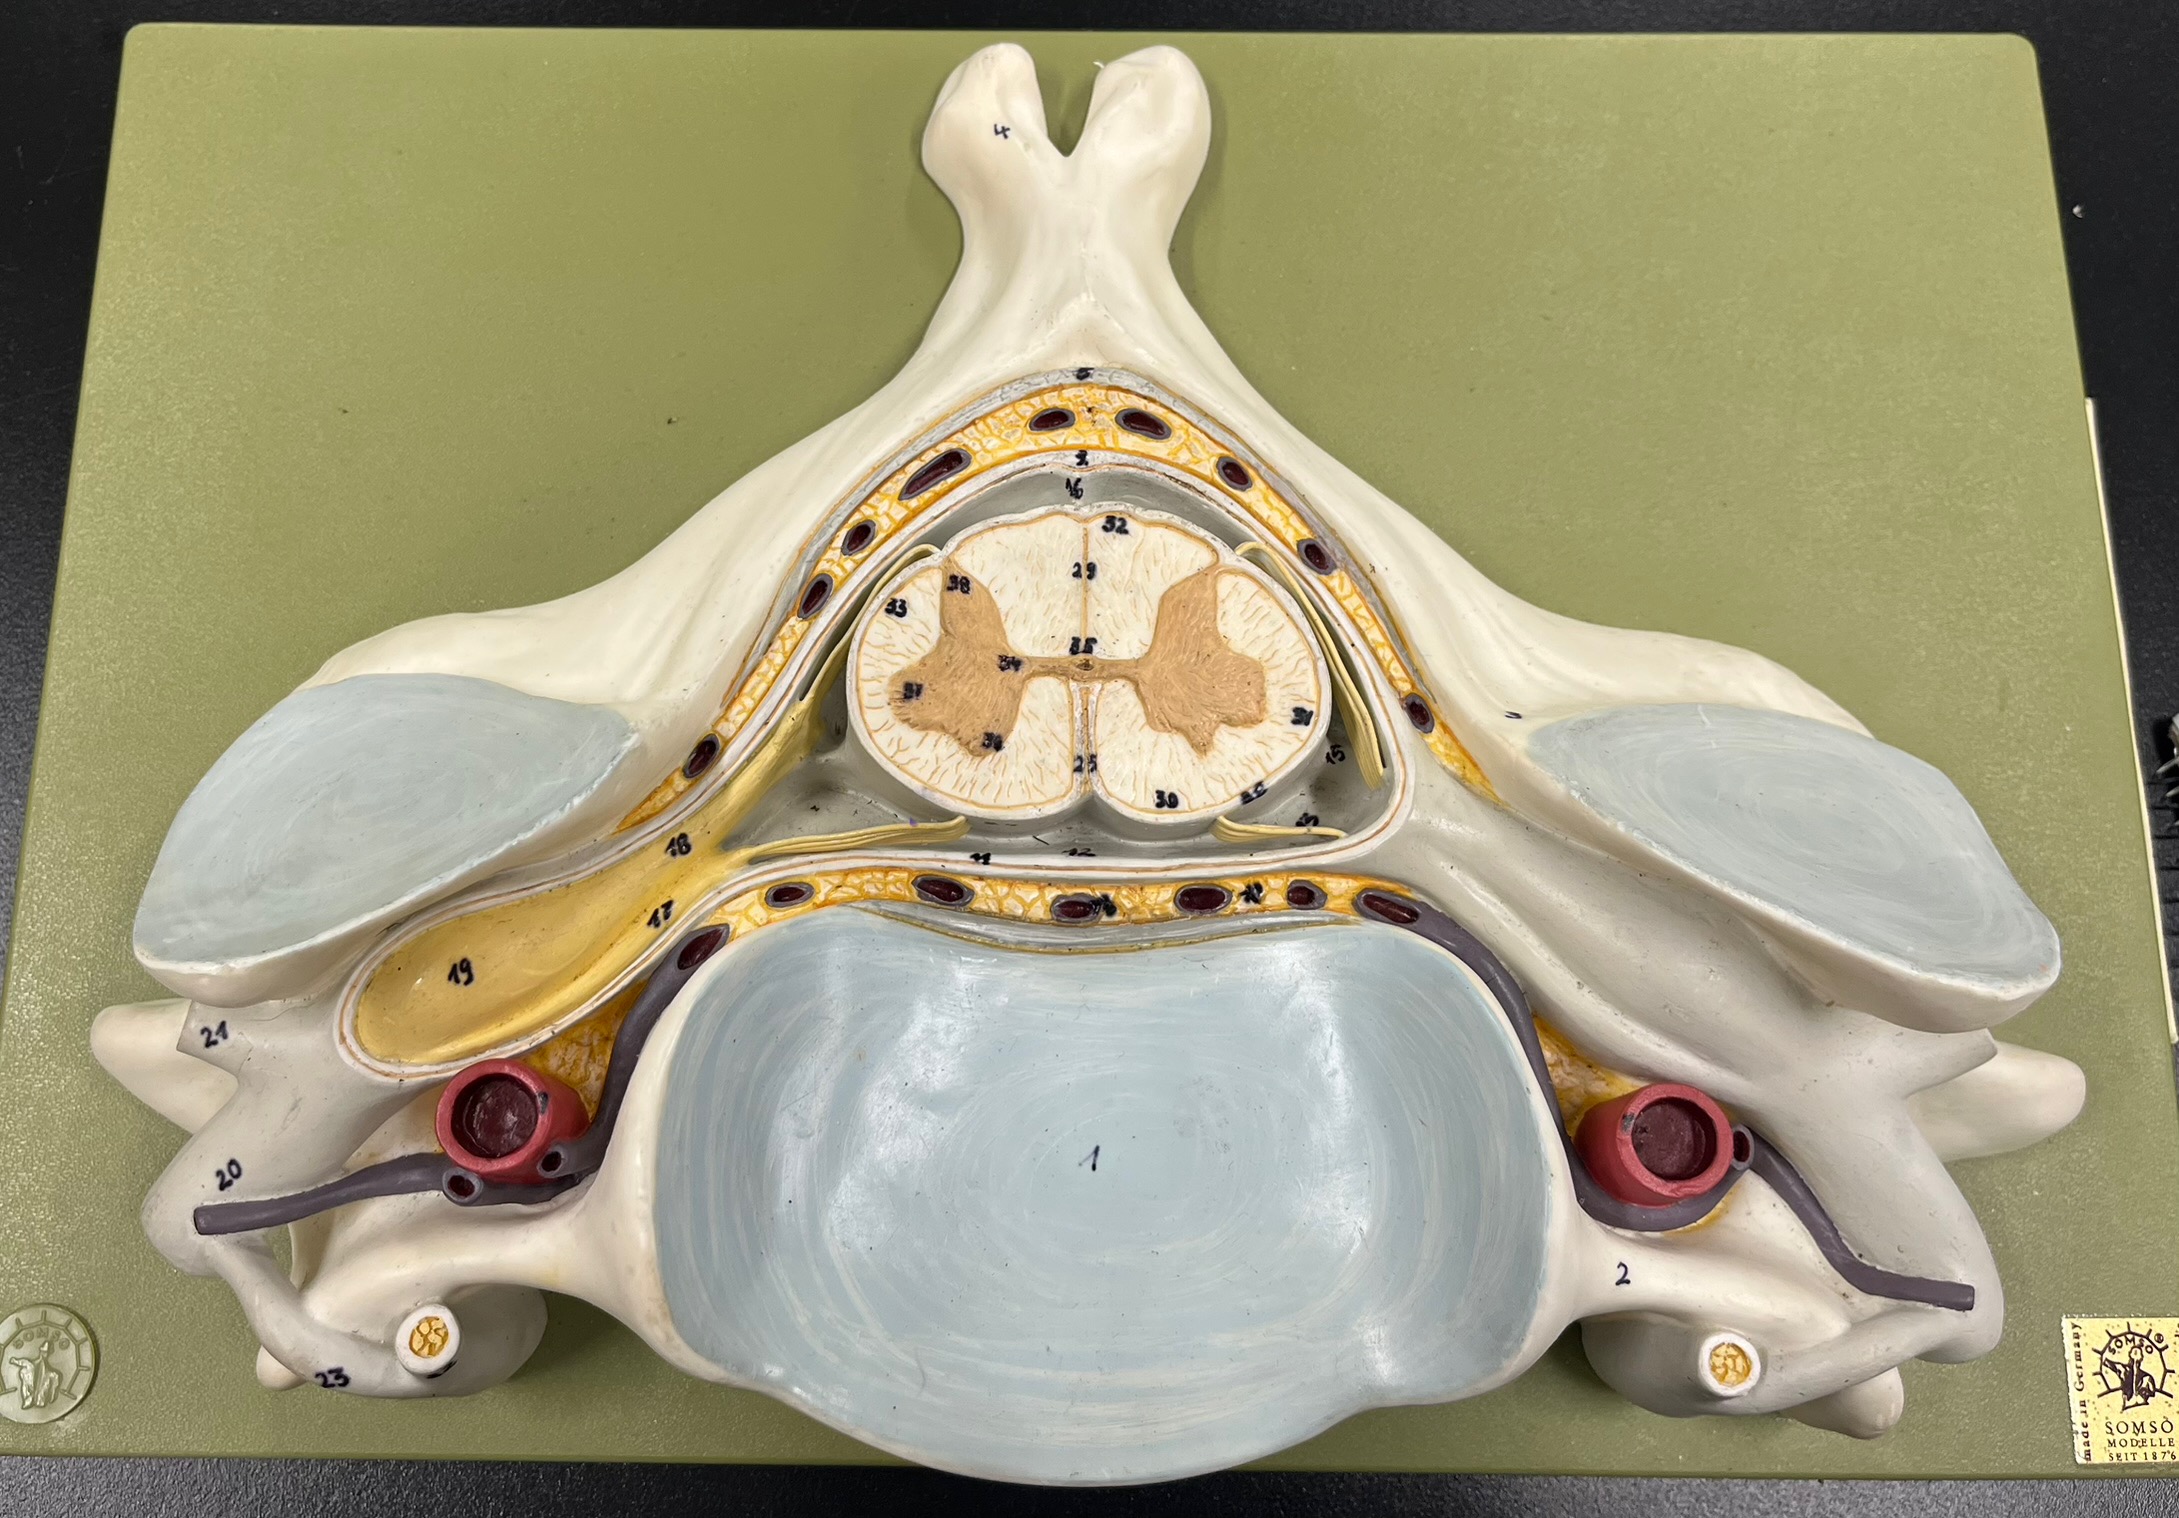

What is the groove here?

anterior median fissure

posterior median sulcus

posterior (dorsal) horn

posterior (dorsal) horn; R—>L

anterior (ventral) horn

lateral horn (selected models)

gray commissure

central canal

anterior column

lateral column

posterior column

white commissure

posterior (dorsal) root ganglion

What is the bulb here?

posterior (dorsal) root ganglion

posterior (dorsal) root

posterior (dorsal) root

anterior (ventral) root

anterior (ventral) root

dorsal ramus

dorsal ramus

ventral ramus

ventral ramus

rami communicantes

rami communicantes

sympathetic chain ganglia

sympathetic chain ganglia